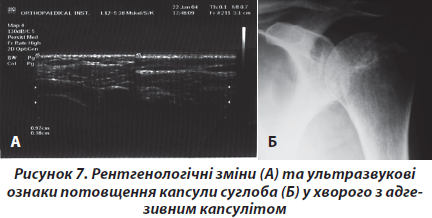

Четверту групу хворих становили 286 осіб (чоловіків — 54, жінок — 232, середній вік 46,4 року). Хворі скаржились на постійний біль в еполетній зоні плеча, що посилювався під час рухів та вночі, різке обмеження обсягу рухів у суглобі. Захворювання у 246 (86 %) хворих розпочалось поступово, протягом у середньому 28,4 тижня. Лише 40 пацієнтів пов’язують розвиток захворювання з травмою. Проте в жодного з цих хворих захворювання не розпочалось одразу після травми, а в термін близько 1 місяця. Збільшення больового синдрому супроводжувалось поступовою втратою рухів, спочатку ротаційних, а потім і відведення. Під час огляду відмічалась гіпотрофія дельтаподібного, надостного і підостного м’язів. Рухи в плечовому суглобі були різко обмежені. Середній показник пасивного відведення при фіксації лопатки становив 25,6°, зовнішньої ротації — 7,5°, внутрішньої ротації — 12,5°. Під час рентгенологічного обстеження у хворих виявляли плямистий остеопороз суглобових кінців, що свідчило про глибокі трофічні порушення [2] (рис. 7). Під час ультразвукового дослідження виявляли потовщення капсули плечового суглоба в зоні ротаторного інтервалу, теносиновіїт сухожилка довгої голівки двоголового м’яза. Під час динамічного ультразвукового обстеження виявляли відсутність артикуляції в субакроміальному суглобі, що ми назвали синдромом субакроміального псевдоконфлікту. Він відрізняється від субакроміального конфлікту тим, що великий горбок через фіброзування капсули просто не доходить до акроміального відростка лопатки.